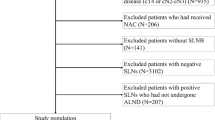

The Bay Area SLN Study for Detection of Axillary Metastasis in Breast Cancer is a multi-institutional collaboration involving 16 institutions in the Greater Bay Area of Northern California and Oregon, of which 15 are community hospitals. A total of 1,040 patients underwent SLN biopsy for biopsy-proven breast cancer between 1996 and 2002. After excluding 256 patients (criteria shown in Additional file 1), we analyzed 784 prospectively accrued subjects with primary invasive breast carcinoma and clinically negative axilla who underwent SLN biopsy with completion axillary lymph node dissection. 285 (36.4%) had tumor-involved SLNs. Among the 285 SLN-positive patients, 213 had pathologic information regarding presence or absence of angiolymphatic invasion (lymphovascular invasion, LVI); 171 patients had complete pathologic information on both angiolymphatic invasion and hormone receptor status. The Northwestern test dataset was compiled by chart review of all patients who underwent a SLN biopsy at Northwestern Memorial Hospital in Chicago, IL, between 2002 and 2006. It is comprised of 77 consecutively identified sentinel node positive patients with invasive breast cancer who underwent completion ALND and had complete pathologic information on tumor type, tumor size, tumor grade, hormone receptor status, HER2/neu status, angiolymphatic invasion status, number of nodes removed, and size of sentinel node metastases. Inclusion and exclusion criteria are similar to that outlined for the Stanford patients in Additional file 1. The Northwestern database was compiled by physicians not involved in generation of the predictive models. The Bay Area SLN study was performed under a protocol approved by the Stanford University Administrative Panel on Human Subjects in Medical Research and the Institutional Review Boards of each participating institution. An independent protocol was approved by the Institutional Review Board of Northwestern University for retrospective chart review and data collection to test the Stanford Online Calculator and MSKCC Nomogram.

Additional file 1: Schematic of patients accrued to Bay Area SLN Database. An overview of the entire Bay Area SLN Database and exclusion criteria for this study. (PDF 131 KB)